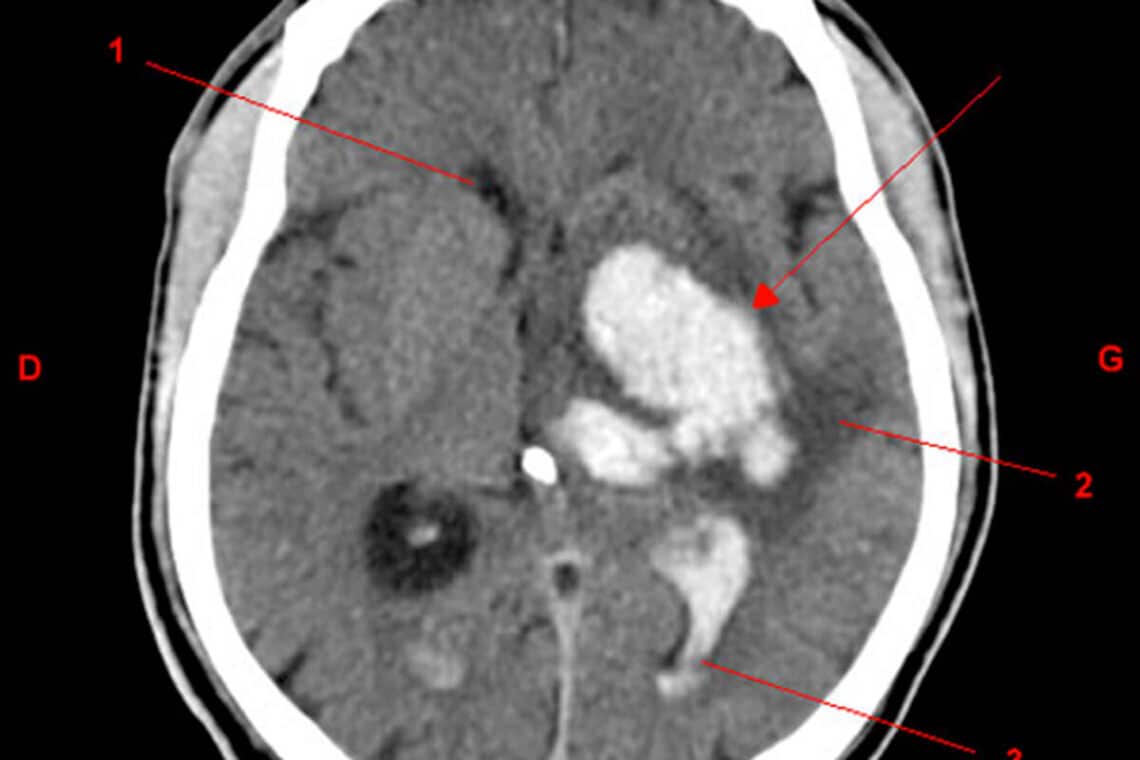

Hoop op het redden van tienduizenden levens per jaar dankzij een nieuw behandelingsprotocol voor hersenbloeding (lees meer)

Gegevens van de INTERACT3 fase III studie tonen aan dat een nieuwe combinatie van momenteel beschikbare behandelingen de overlevingskansen zonder ernstige invaliditeit bij een intracerebrale bloeding aanzienlijk verbetert. De resultaten werden gepresenteerd op de European Stroke Organisation Conference, München 24-26 mei, en gepubliceerd in The Lancet.